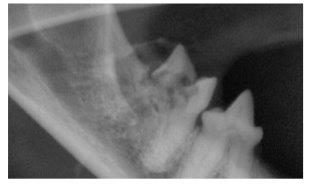

Below: The same tooth showing extensive destruction of both the tooth root and crown (the part above the gum line). This shows on the X-ray as grey fluffy looking areas (highlighted by the orange arrow and circle), compared this to the adjacent healthy tooth root and crown showing on the X-ray as a solid white tooth (highlighted by the green arrow and circle). This is a feline resorptive lesion and is a very painful condition. (Image reproduced with kind permission from Dr Tara Cashman, President of the Australian Veterinary Dental Society), demonstrating the importance of dental X-rays to uncover serious dental disease which could otherwise be missed.

cat gingivitis xray